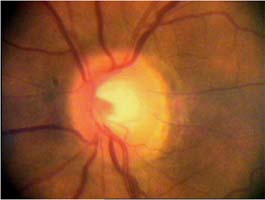

Velikost terče

Tento terč má širokou cirkulární peripapilární atrofii, která opticky vytváří falešný dojem širokého neuroretinálního lemu, zvláště nasálně.

Rozsah a hloubka exkavace

Správně určit rozsah a hloubku exkavace vyžaduje vidět terč prostorově:

Očekávali byste protažení exkavace k hornímu pólu terče, jak nám ukazuje tento snímek z tomografu HRT II.

exkavace levé oko

Na kterém oku je exkavace větší, na pravém nebo na levém? Podle pohledu na fotografie jistě na levém.

exkavace pravé oko

Na kterém oku je exkavace větší, na pravém nebo na levém? Podle pohledu na fotografie jistě na levém.

Co je příčinou toho, že při pohledu na snímky hodnotíme rozsah exkavace nesprávně? Je to skutečnost, že i růžová oblast neuroretinálního lemu může být již prohloubená, což vídáme zvláště na počátku rozvoje glaukomové neuropathie.

A jak se můžeme vyhnout záměně okrsku bledší barvy za skutečnou exkavaci? Tím, že budeme mít na paměti, že exkavace může být větší než nablednutí. Také zařazení zeleného filtru na pomůže snížit nežádoucí barevný kontrast.